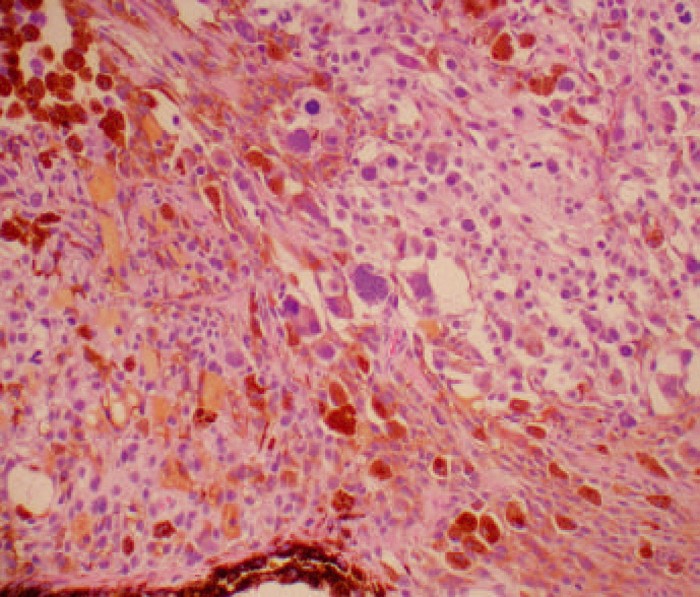

Case 18. Mixed spindle cell and epithelioid melanoma (iris). A …